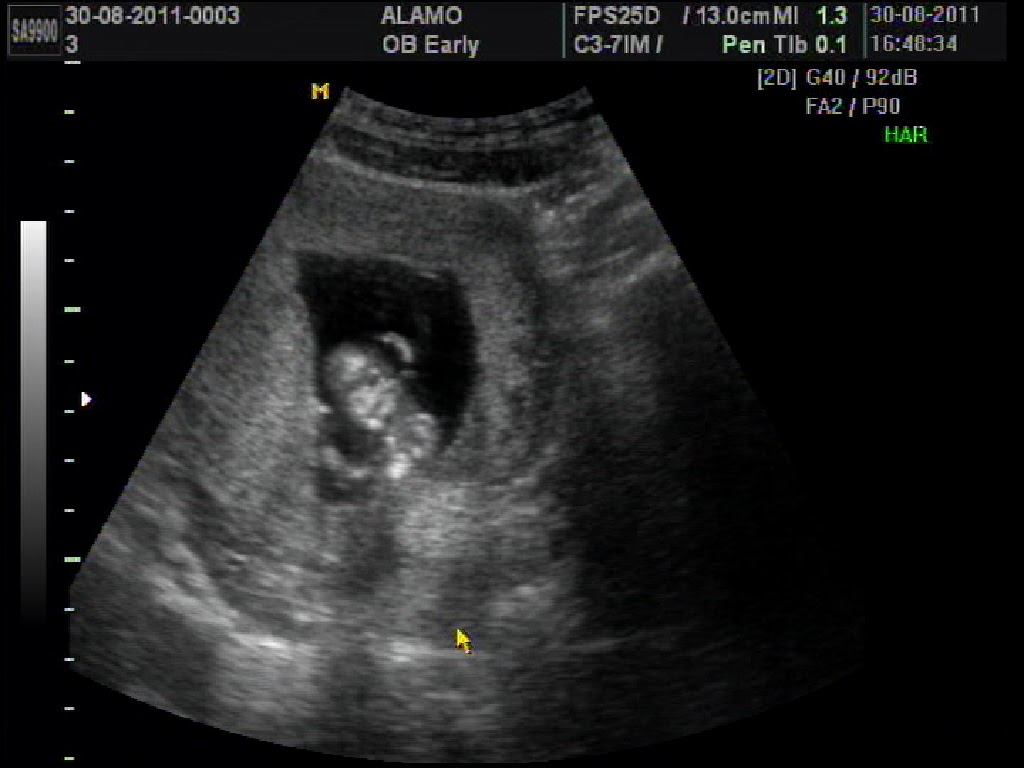

Ultrasom 28 semanas! Princesinha a caminho!

Começamos pelos cabelinhos da Laurinha (apontados na flecha), quem será que puxou, papai? Mamãe? Encaracolado? Liso?

Os pézinhos mais lindos da mamãe, chutando ela para valer!

Os "documentos" da minha filhotinha (xuxa) e a placenta do lado...

E o rostinho mais redondinho da mamãe em zoom, especialmente focado para o papai ver...

E assim vai começando a nossa história, nosso Amor...